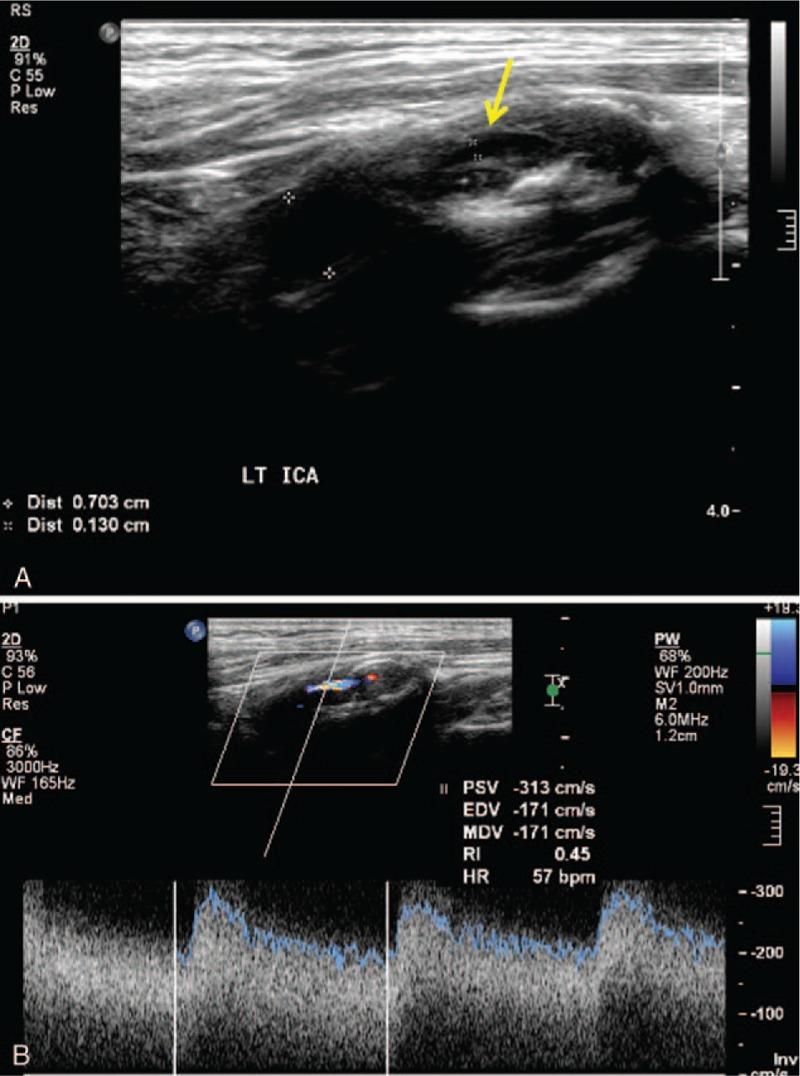

We aimed to investigate the association between carotid artery stenosis and peripheral artery disease (PAD) by screening carotid ultrasonography (CUS).From January 2012 to December 2015, 231 consecutive patients who had undergone preoperative CUS for PAD were included in this study. A radiologist assessed the degree of internal carotid artery (ICA) stenosis by using the North American Symptomatic Carotid Endarterectomy Trial (NASCET). Severe (>70%) ICA stenosis was evaluated based on the type of vascular surgery, PAD lesion, and ankle-brachial index (ABI). Data were analyzed using multiple logistic regression analysis and the χ test.Among 231 PAD patients, multilevel lesions revealed significantly higher incidence of severe ICA stenosis than iliac and infrainguinal lesion (22.5% vs 9.4% vs 8%: P = .016). Age (odds ratio [OR]: 1.05, 95% confidence interval [CI]: 1.00-1.12: P = .035), chronic kidney disease (CKD, OR: 6.19, 95% CI: 2.04-45.04: P = .013), and cerebral vascular disease (CVD, OR: 4.08, 95% CI: 1.13-16.46: P = .037) were significant risk factors of severe ICA stenosis in multivariate analysis. Prevalence of severe ICA stenosis according to ABI in PAD was not significant.Preoperative screening by CUS provides valuable information onasymptomatic carotid artery stenosis (ACAS) that can identify severe ACAS patients who are at high risk of stroke and to consider more intensive management of carotid disease in PAD patients. CUS can be a useful noninvasive preoperative screening imaging tool for PAD patients with multilevel lesions, aged > 65 years old, with CKD and CVD.

我们旨在通过颈动脉超声检查(CUS)来研究颈动脉狭窄与外周动脉疾病(PAD)之间的关联。2012年1月至2015年12月,本研究纳入了231例因PAD接受术前CUS检查的连续患者。一名放射科医生采用北美症状性颈动脉内膜切除术试验(NASCET)评估颈内动脉(ICA)狭窄程度。基于血管手术类型、PAD病变和踝臂指数(ABI)对重度(>70%)ICA狭窄进行评估。使用多元逻辑回归分析和χ检验对数据进行分析。在231例PAD患者中,多级病变患者的重度ICA狭窄发生率显著高于髂动脉和腹股沟下病变患者(22.5%对9.4%对8%:P = 0.016)。年龄(比值比[OR]:1.05,95%置信区间[CI]:1.00 - 1.12:P = 0.035)、慢性肾脏病(CKD,OR:6.19,95% CI:2.04 - 45.04:P = 0.013)和脑血管疾病(CVD,OR:4.08,95% CI:1.13 - 16.46:P = 0.037)在多变量分析中是重度ICA狭窄的显著危险因素。根据PAD患者的ABI得出的重度ICA狭窄患病率无显著差异。术前通过CUS筛查可提供关于无症状性颈动脉狭窄(ACAS)的有价值信息,能够识别出有中风高风险的重度ACAS患者,并考虑对PAD患者的颈动脉疾病进行更强化的管理。对于患有多级病变、年龄>65岁、患有CKD和CVD的PAD患者,CUS可作为一种有用的无创术前筛查成像工具。